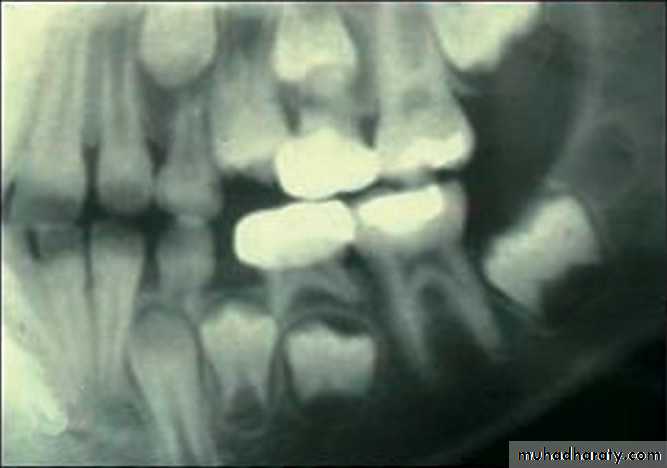

A panoramic radiographic unit can be used for examination of children.Advantages

Since the examination is obtained without placement of the film in the mouth, it does not alarm the anxious child who may refuse an intraoral film.

This view can be useful in handicapped children and for viewing a wide area of the TMJ and associated region.

Panoramic is recommended at approximately the time of the early mixed dentition to assess

1. the dental age of the patient and

2. to aid in the early diagnosis of congenital and developmental anomalies.Panoramic radiograph

Panoramic used to diagnose:

Condylar fractures,traumatic cysts,

and anomalies that might have gone undetected with the routine periapical survey.